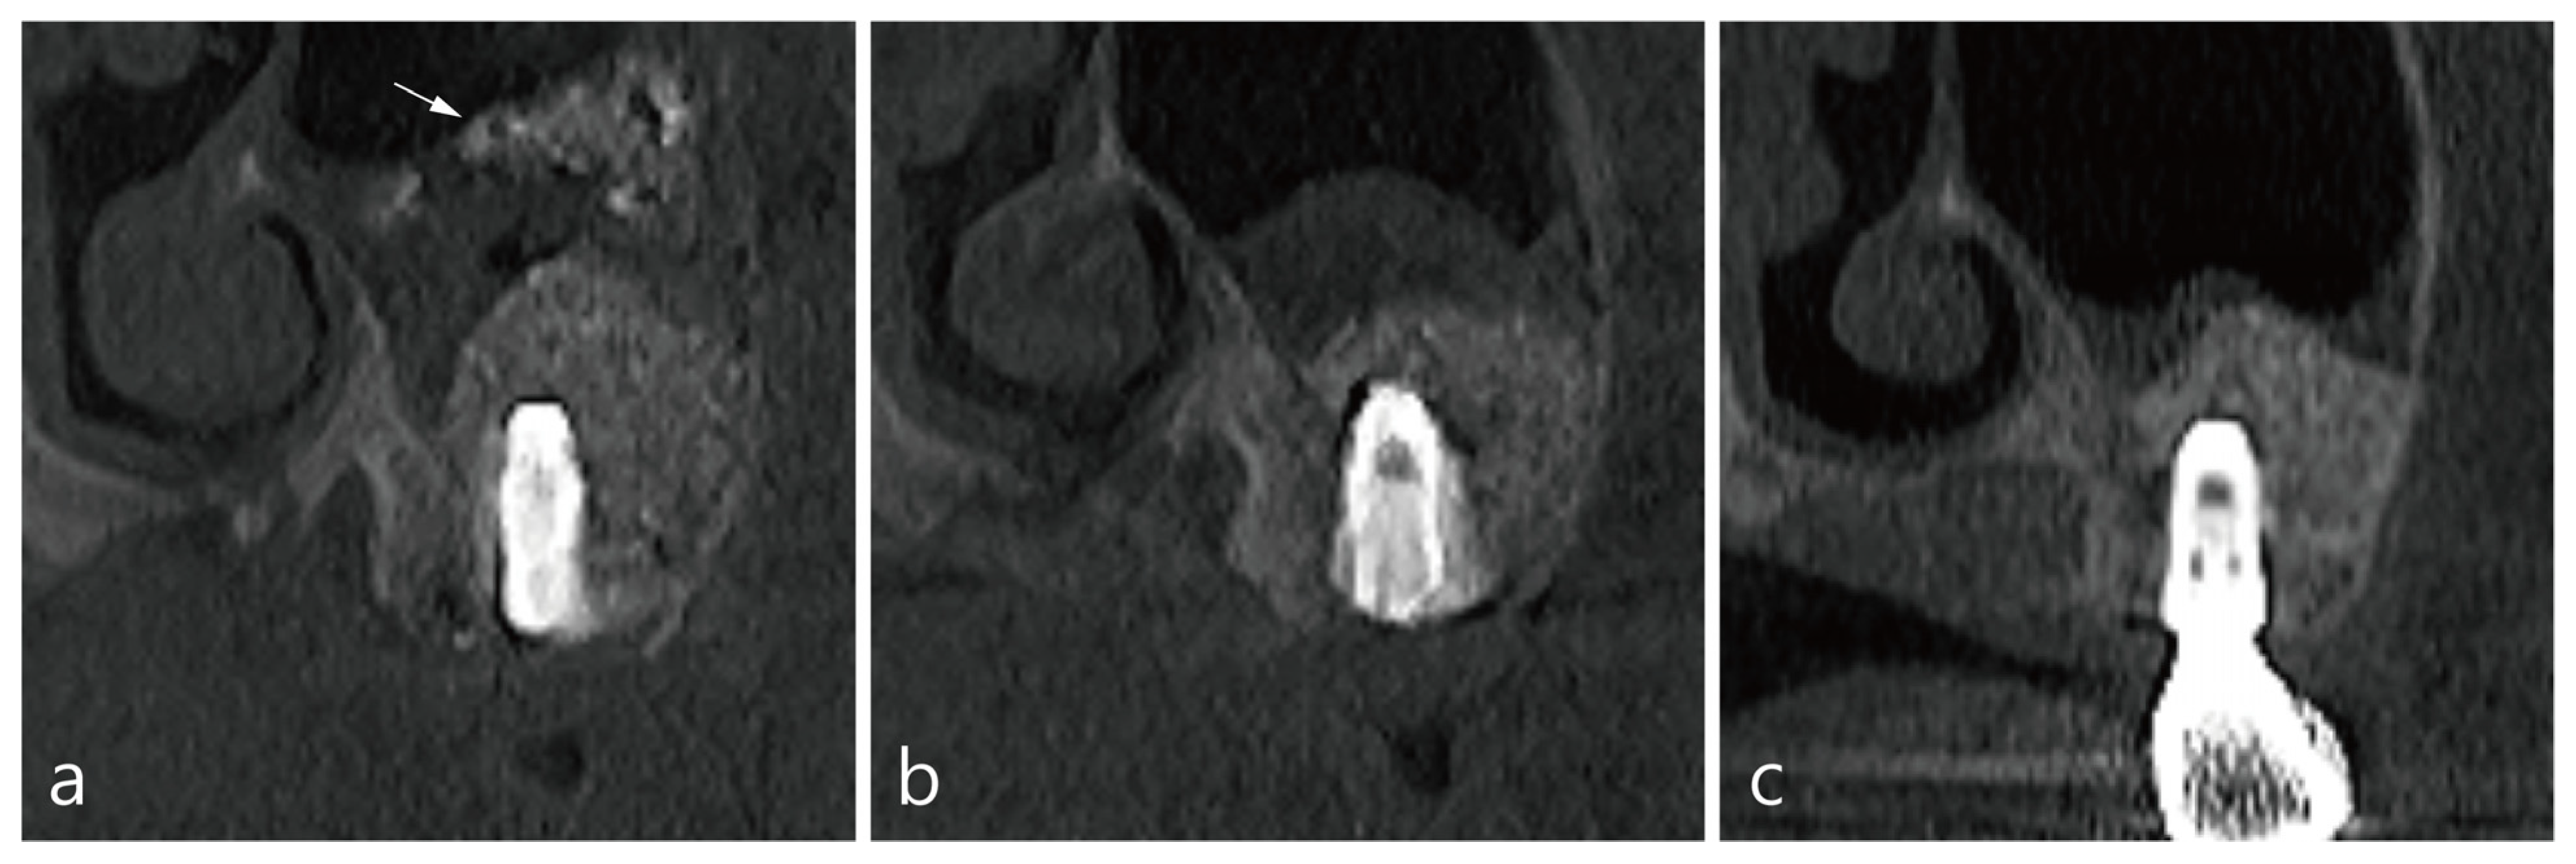

2. Presentation of Cases

3. Case 1

4. Case 2

5. Case 3

6. Case 4